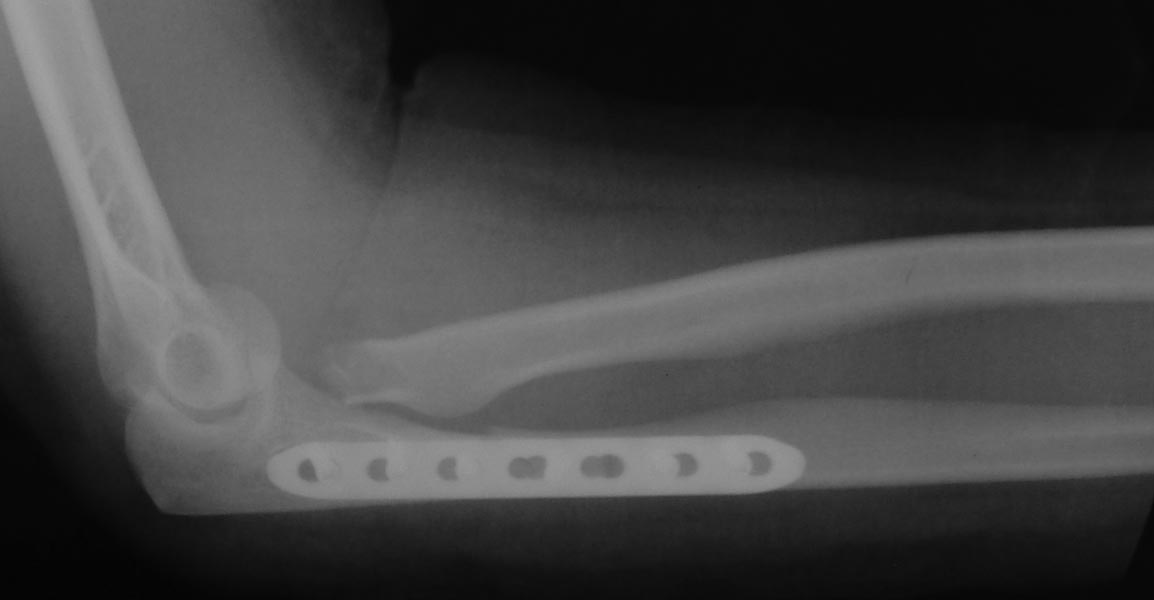

Хочу попросить совета у сообщества по поводу следующего клинического случая. Женщина, 65 лет. Закрытый перелом Монтеджи слева в октябре 2013 года. (рис. 1, 2). Для наглядности сделал скиаграмму перелома (рис. 3, 4). На 8-е сутки накостный остеосинтез пластинами с угловой стабильностью. Головка луча была восстановлена из отломков (рис. 5) и собрана на спицах одну из которых скусили и оставили под пластиной.(рис. 6). Вроде получилось стабильно, видео на операции по этой ссылке:

http://youtu.be/vdeYGTWrTmkНа рентгенограмме тоже вроде ничего. (рис. 7, 8).Из реабилитации порекомендовали заниматься с первого дня движениями в суставе (пронация/супинация, сгибание/разгибание), выполнять несложную домашнюю работу. Видео объма движения на 7-е сутки после операции по ссылке: http://youtu.be/KyPAUmEIhs4